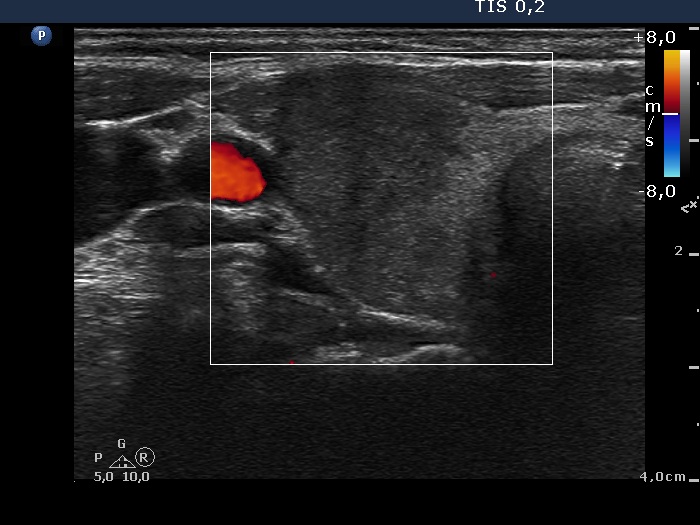

Initial examination (first row of images):

Clinical presentation: A 39-year-old woman was referred for evaluation of neck complaints lasting for more than a month. The patient had fever, neck pain. She has got two courses of antibiotics and non-steroid anti inflammatory drugs which had no effect.

Palpation: The right lobe was painful and hard while the left lobe was tender.

Laboratory examination: TSH 0.01 mIU/L, FT4 29.1 pM/L, FT3 7.45 pM/L, CRP 31.2 mg/L.

Ultrasonography: The thyroid presented with hypoechoic areas which had blurred borders. The echogenicity index was approximately 65% in the right and 20% in the left lobe. The thyroid was almost completely avascular.

Diagnosis: subacute, granulomatous de Quervain's thyroiditis.